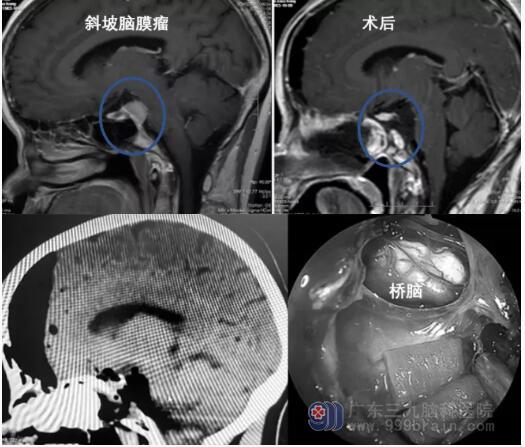

颅底中线的脑膜瘤

脑膜瘤是常见的原发性颅内病变。神经内镜辅助经鼻切除术已成为颅底中线脑膜瘤首选治疗方法,适合运用于治疗发生在前颅窝的中小型脑膜瘤,如蝶骨平台和鞍结节脑膜瘤和斜坡脑膜瘤等。神经内镜经鼻手术可减少脑损伤,患者术后颅神经的并发症和术后住院时间等均可得到改善。如果肿瘤压迫视神经导致视力受损时,神经内镜经鼻入路还能对视神经管进行早期减压,早期挽救视力。